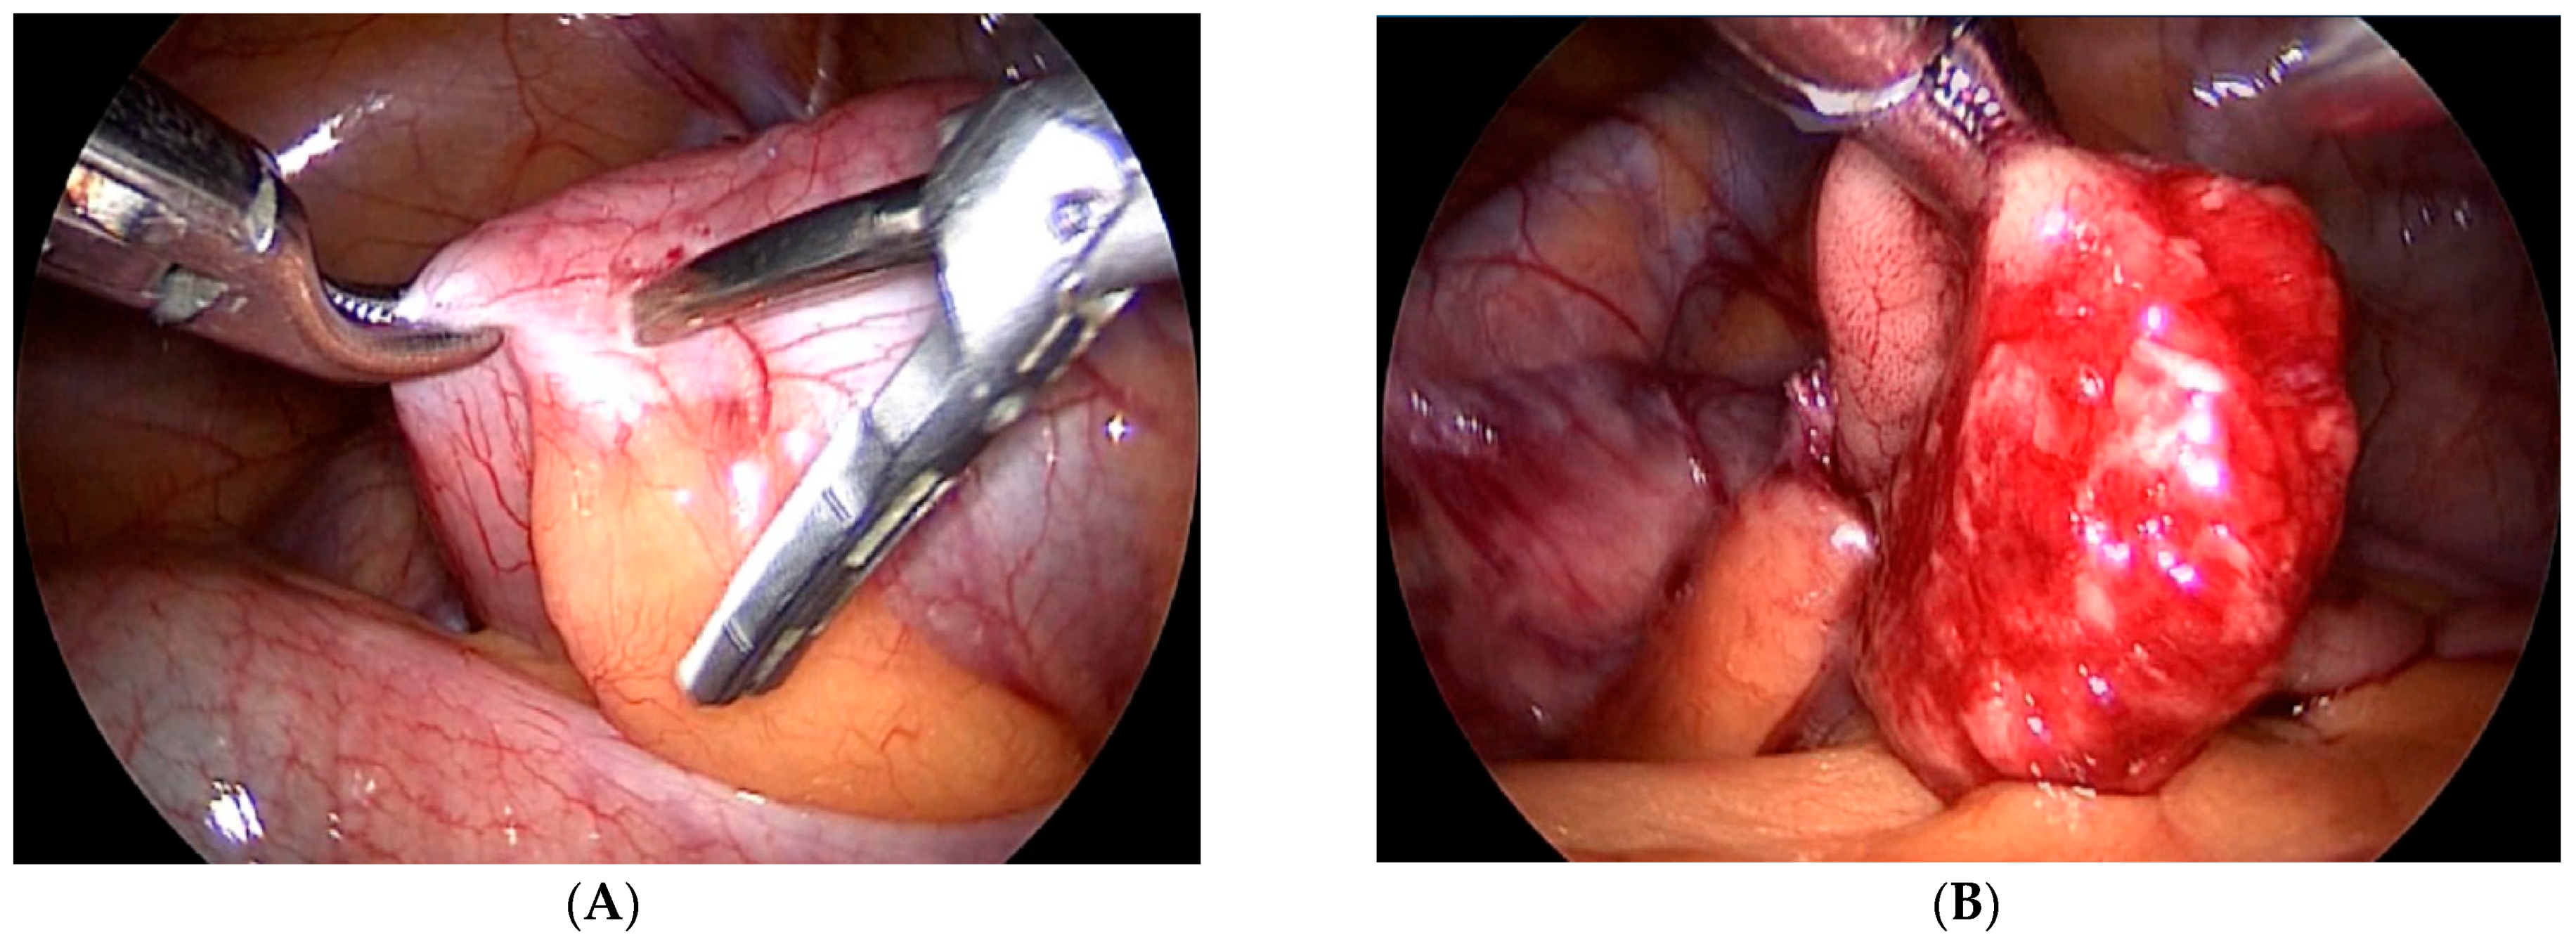

Our third case is a 2-year-old child who was admitted to hospital due to blood and mucus in the stool. Intraoperative colonoscopy revealed polypoid form diameter around 2 cm, 30 cm from the anocutaneous line that showed ulcerations and was on the wide base. Biopsies were sent for pathohistological examination. The endoscopic histologic diagnosis was a polyp of the sigma and chronic colitis. A polypectomy was performed using a laparoscopic–endoscopic “rendezvous” procedure. Infraumbilical open access with the 5-millimeter Hasson technique was used to create pneumoperitoneum. The working ports were placed in epigastric and in the upper right quadrant. By lighting from the lumen of the colon, an enterotomy was performed (Figure 1A). The polyp was visualized, resected in its base (Figure 1B), and sent for definitive pathohistological examination. A direct enterorrhaphy during the laparoscopy was performed in the standardized manner. The operation was completed, and the postoperative period was uneventful.

Figure 1.

(A) Endoscopic guidance from the lumen of the intestine and a place of enterotomy, (B) Complete visualization of the polyp and its resection.